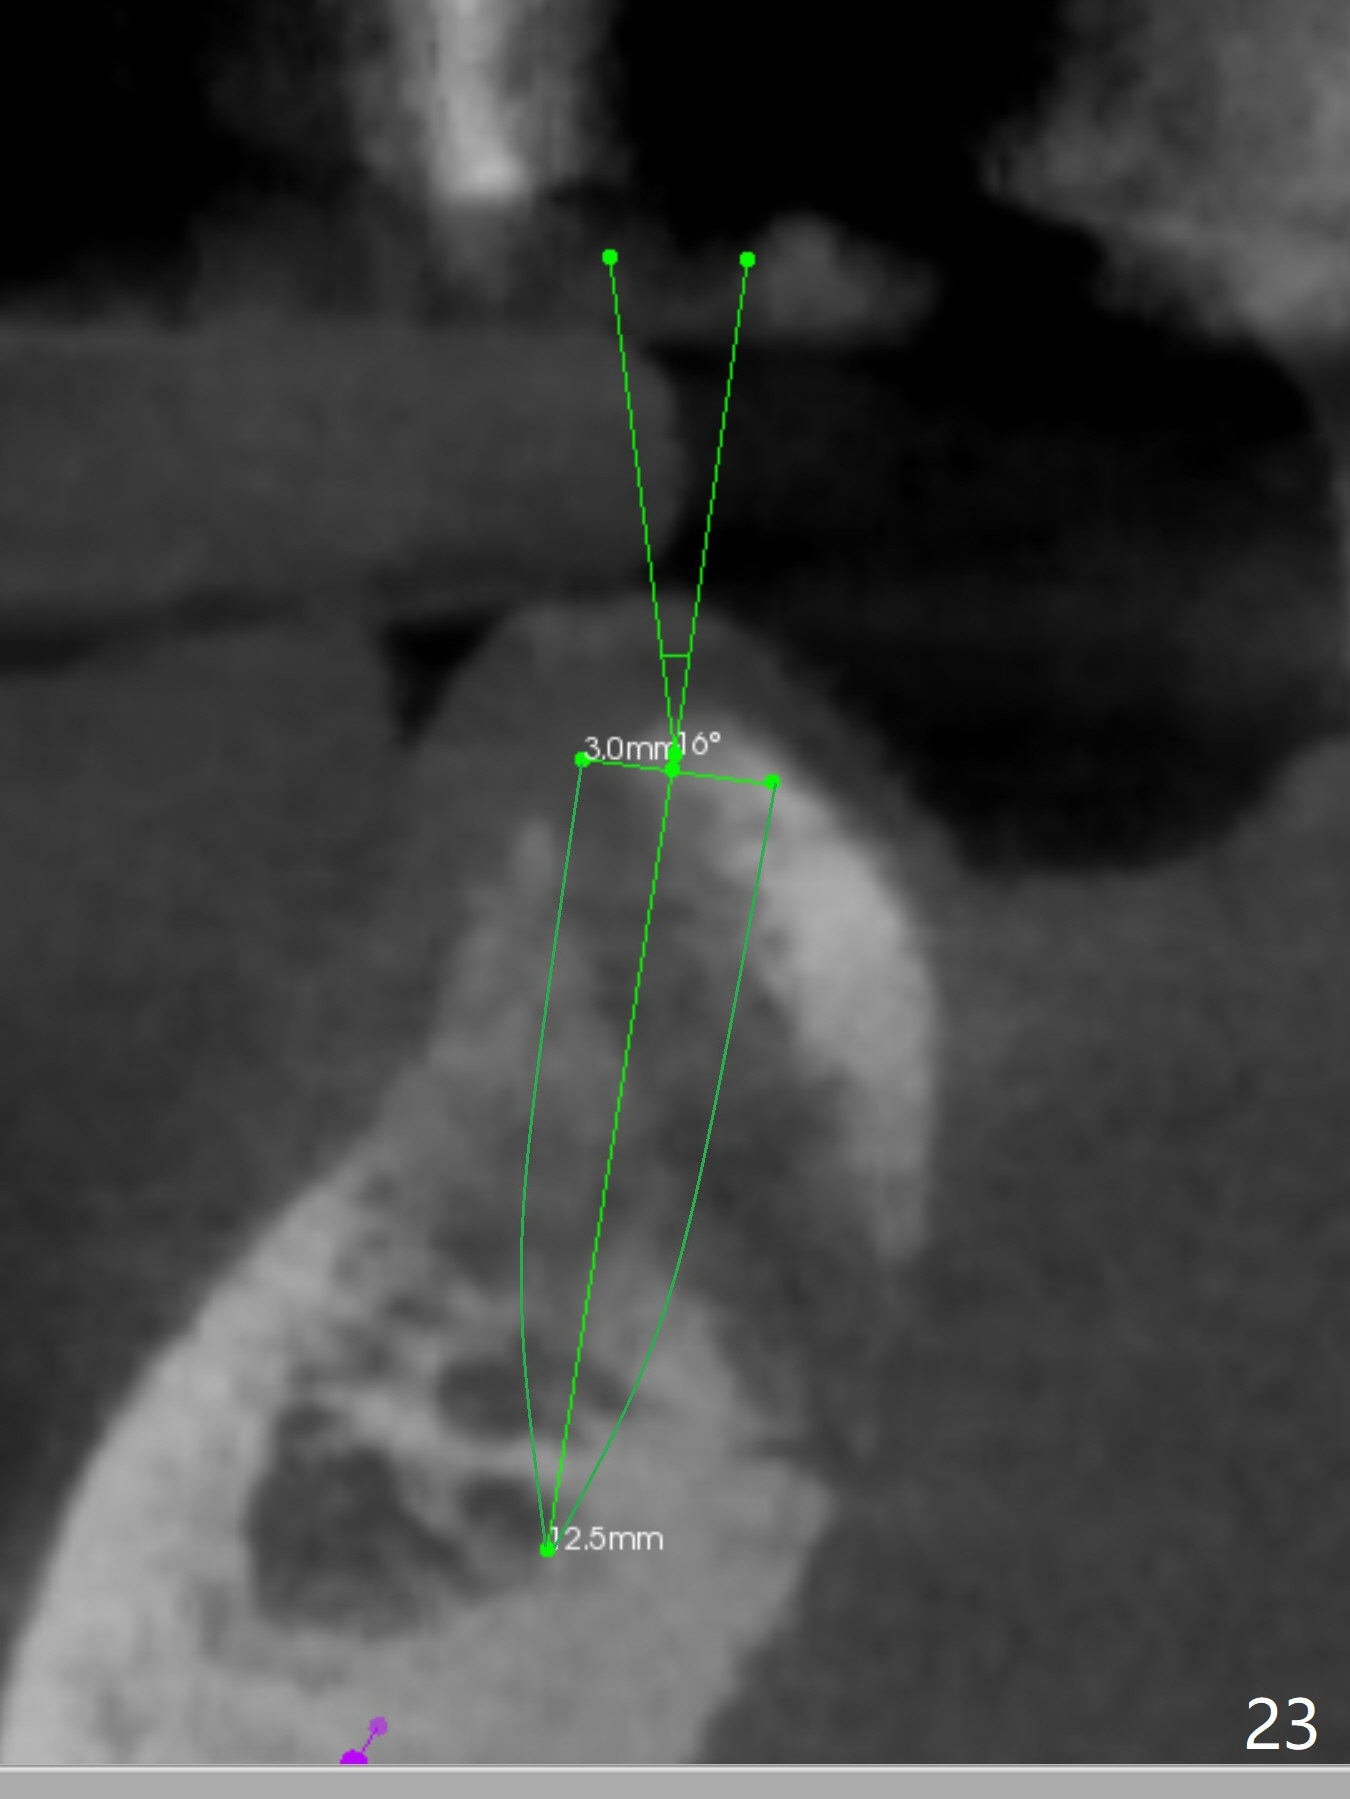

When the bone height seems to be limited in the lower anterior region, use short implants. CT is retaken nearly 2 months post implant removal (Fig.22,23 (O: opposing tooth)). It seems possible to re-place a smallest 2-piece implant where the bone is relatively wide (Fig.22) and a 3-mm 15 degree angled 1-piece implant where the bone is narrow (Fig.23) by simply changing trajectory. New implants are placed nearly 3 months post implant removal (Fig.24,25). In fact the site of #27 re-perforates; a shorter implant is placed with bone graft apically. Immediate provisional is fabricated so that the clasp is not irritating. There is moderate edema and pain lingual to #27 site postop. Augmentin is taken for 3 weeks with alleviation of the symptoms. The implant at #27 is loose 1 month postop and removed.